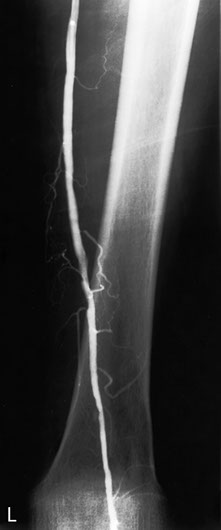

The most favourite subspecialty was angiography and interventional work particularly in the vascular field. This was the first angioplasty performed in the department. This represents atheroma with a focal stricture of the left femoral artery which was dilated with the presented result. Note that the atheromatous process is not limited to one area.

Femoral artery stricture post dilatation. Note the ragged appearance of the dilated atheromatous plaque.